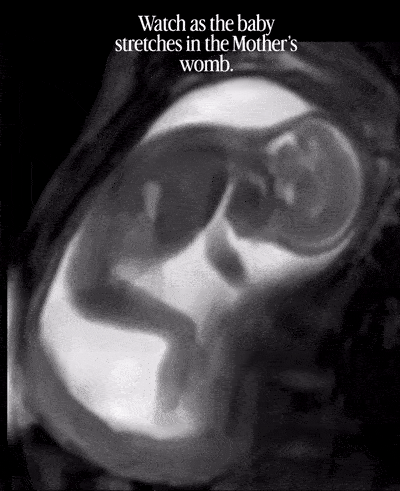

Je suis tombée par hasard sur cette image d’un bébé dans le ventre de sa mère.

Il s’agit d’une IRM probablement menée dans les jours qui ont précédé l’accouchement.

Le voici qui s’étire et reçoit le signal de sa mère d’arrêter. C’est à la fois impressionnant et fascinant.

La technologie d’imagerie médicale moderne a ouvert une porte sur l’intimité in utero.